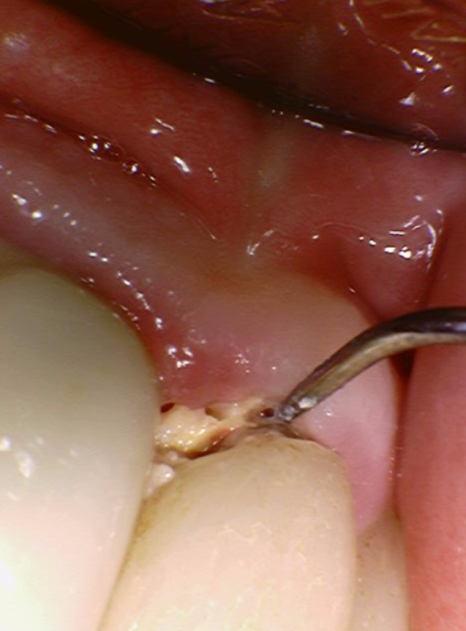

정확한 확인을 위해 기구(탐침)로

조심스럽게 건드려 보았더니,

단단해야 할 치아가 삭아 '쑥!' 하고

기구가 들어가 버렸습니다.

충치가 아주 깊다는 증거였죠.

기존 브릿지를 제거하고

내부 상태를 확인했습니다.

예상대로 음식물 찌꺼기와 오염이 심각했지만,

여기서 불행 중 천만다행인 사실...

230516

남은 치아의 양이 적당하여

발치는 피할 수 있는 상황이었어요.